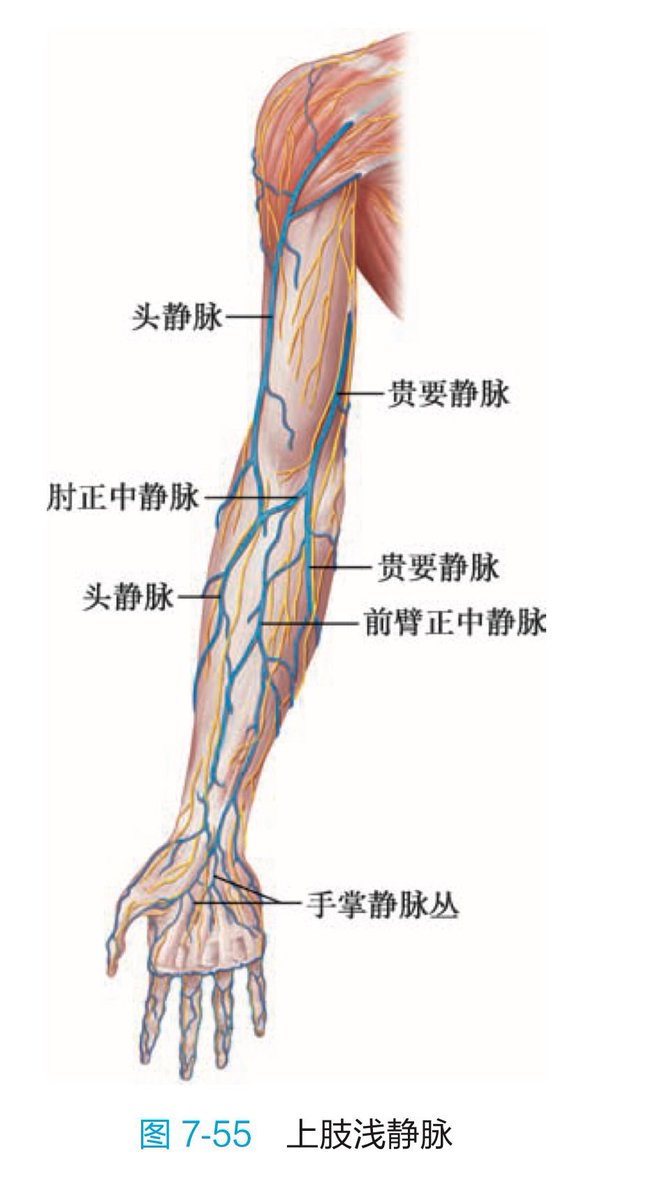

吃完唑吡坦会干一些难绷的事情,昨天睡不着疑似气急败坏了抽了0.5ml右美托咪定就是iv,还奇奇怪怪挑了个很痛的头静脉

你别说还扎得挺好的()按压时间估计也够,一点淤青也没有,不知道哪来的意志力 https://t.co/KxtfAUVSmb